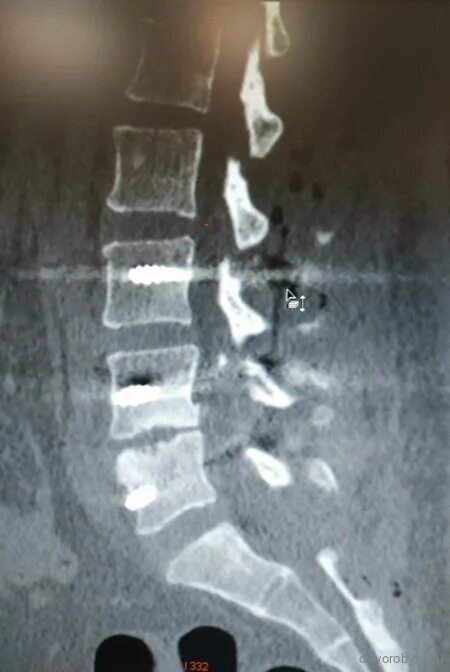

Смещение позвонков поясничного операция